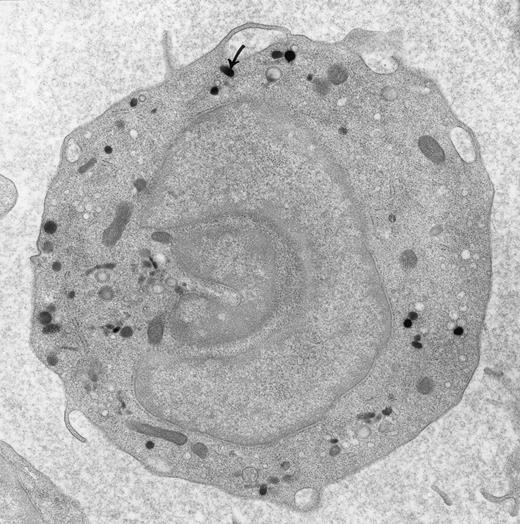

Peroxidase-positive lysosomes (arrow) in a peripheral blood monocyte. Original magnification × 16,000. (Courtesy of Ann M. Dvorak, MD, Department of Pathology, Beth Israel Hospital, Harvard Medical School, Boston, MA 02215.)